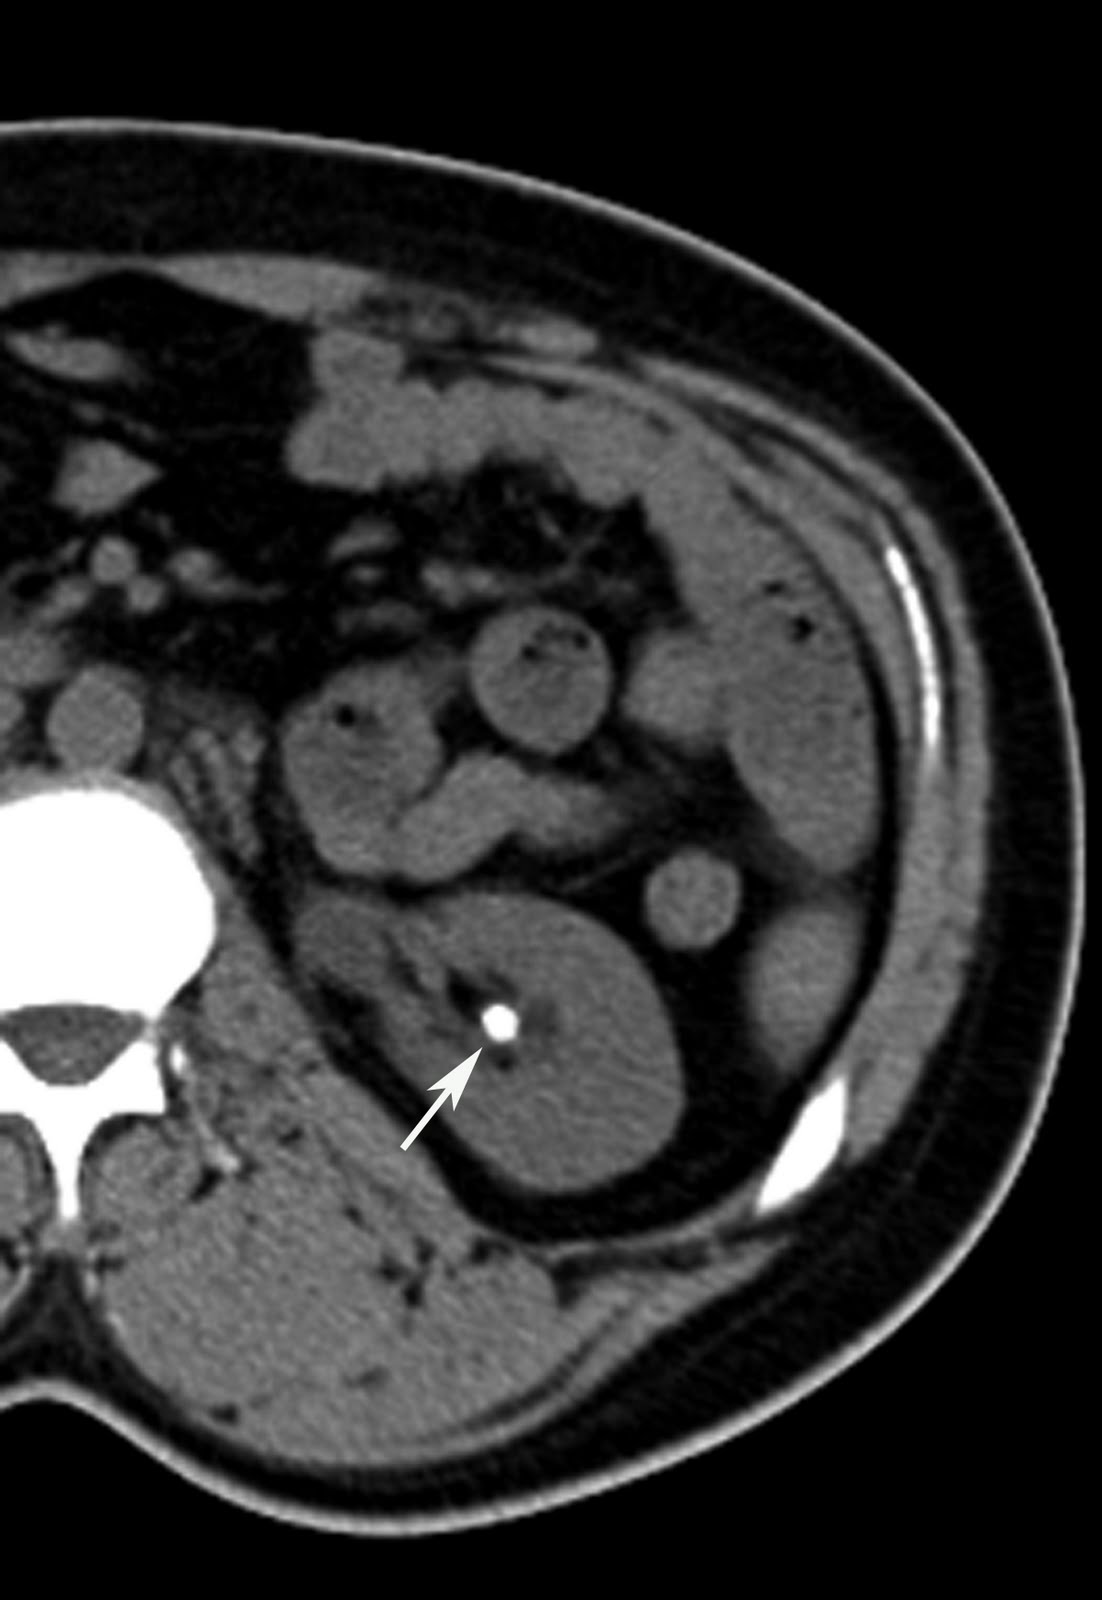

Renal Stones Body MR Case Studies CTisus CT Scanning

Stone in Right Renal Pelvis Kidney Case Studies CTisus CT Scanning Ct Scan Kidney Stone Protocol Not all cases require imaging tests. R/o kidney or ureteral stones. Patients may present with the. Kidney stone disease (nephrolithiasis) is a common problem in primary care practice. Scan from top of kidneys to bottom of symphysis pubis. Is a ct scan necessary to diagnose kidney stones? Learn why your provider might order a scan. If allergic to contrast or. Ct Scan Kidney Stone Protocol.

Stone in Right Renal Pelvis Kidney Case Studies CTisus CT Scanning Ct Scan Kidney Stone Protocol Learn why your provider might order a scan. R/o kidney or ureteral stones. Learn about the procedure, reasons, risks, and preparation for a ct scan of the kidney, which can detect kidney stones and other conditions. Not all cases require imaging tests. Kidney stone disease (nephrolithiasis) is a common problem in primary care practice. Patients may present with the. Scan. Ct Scan Kidney Stone Protocol.

Stone in Right Renal Pelvis Kidney Case Studies CTisus CT Scanning Ct Scan Kidney Stone Protocol Kidney stone disease (nephrolithiasis) is a common problem in primary care practice. If allergic to contrast or poor. Is a ct scan necessary to diagnose kidney stones? Not all cases require imaging tests. Learn about the procedure, reasons, risks, and preparation for a ct scan of the kidney, which can detect kidney stones and other conditions. R/o kidney or ureteral. Ct Scan Kidney Stone Protocol.